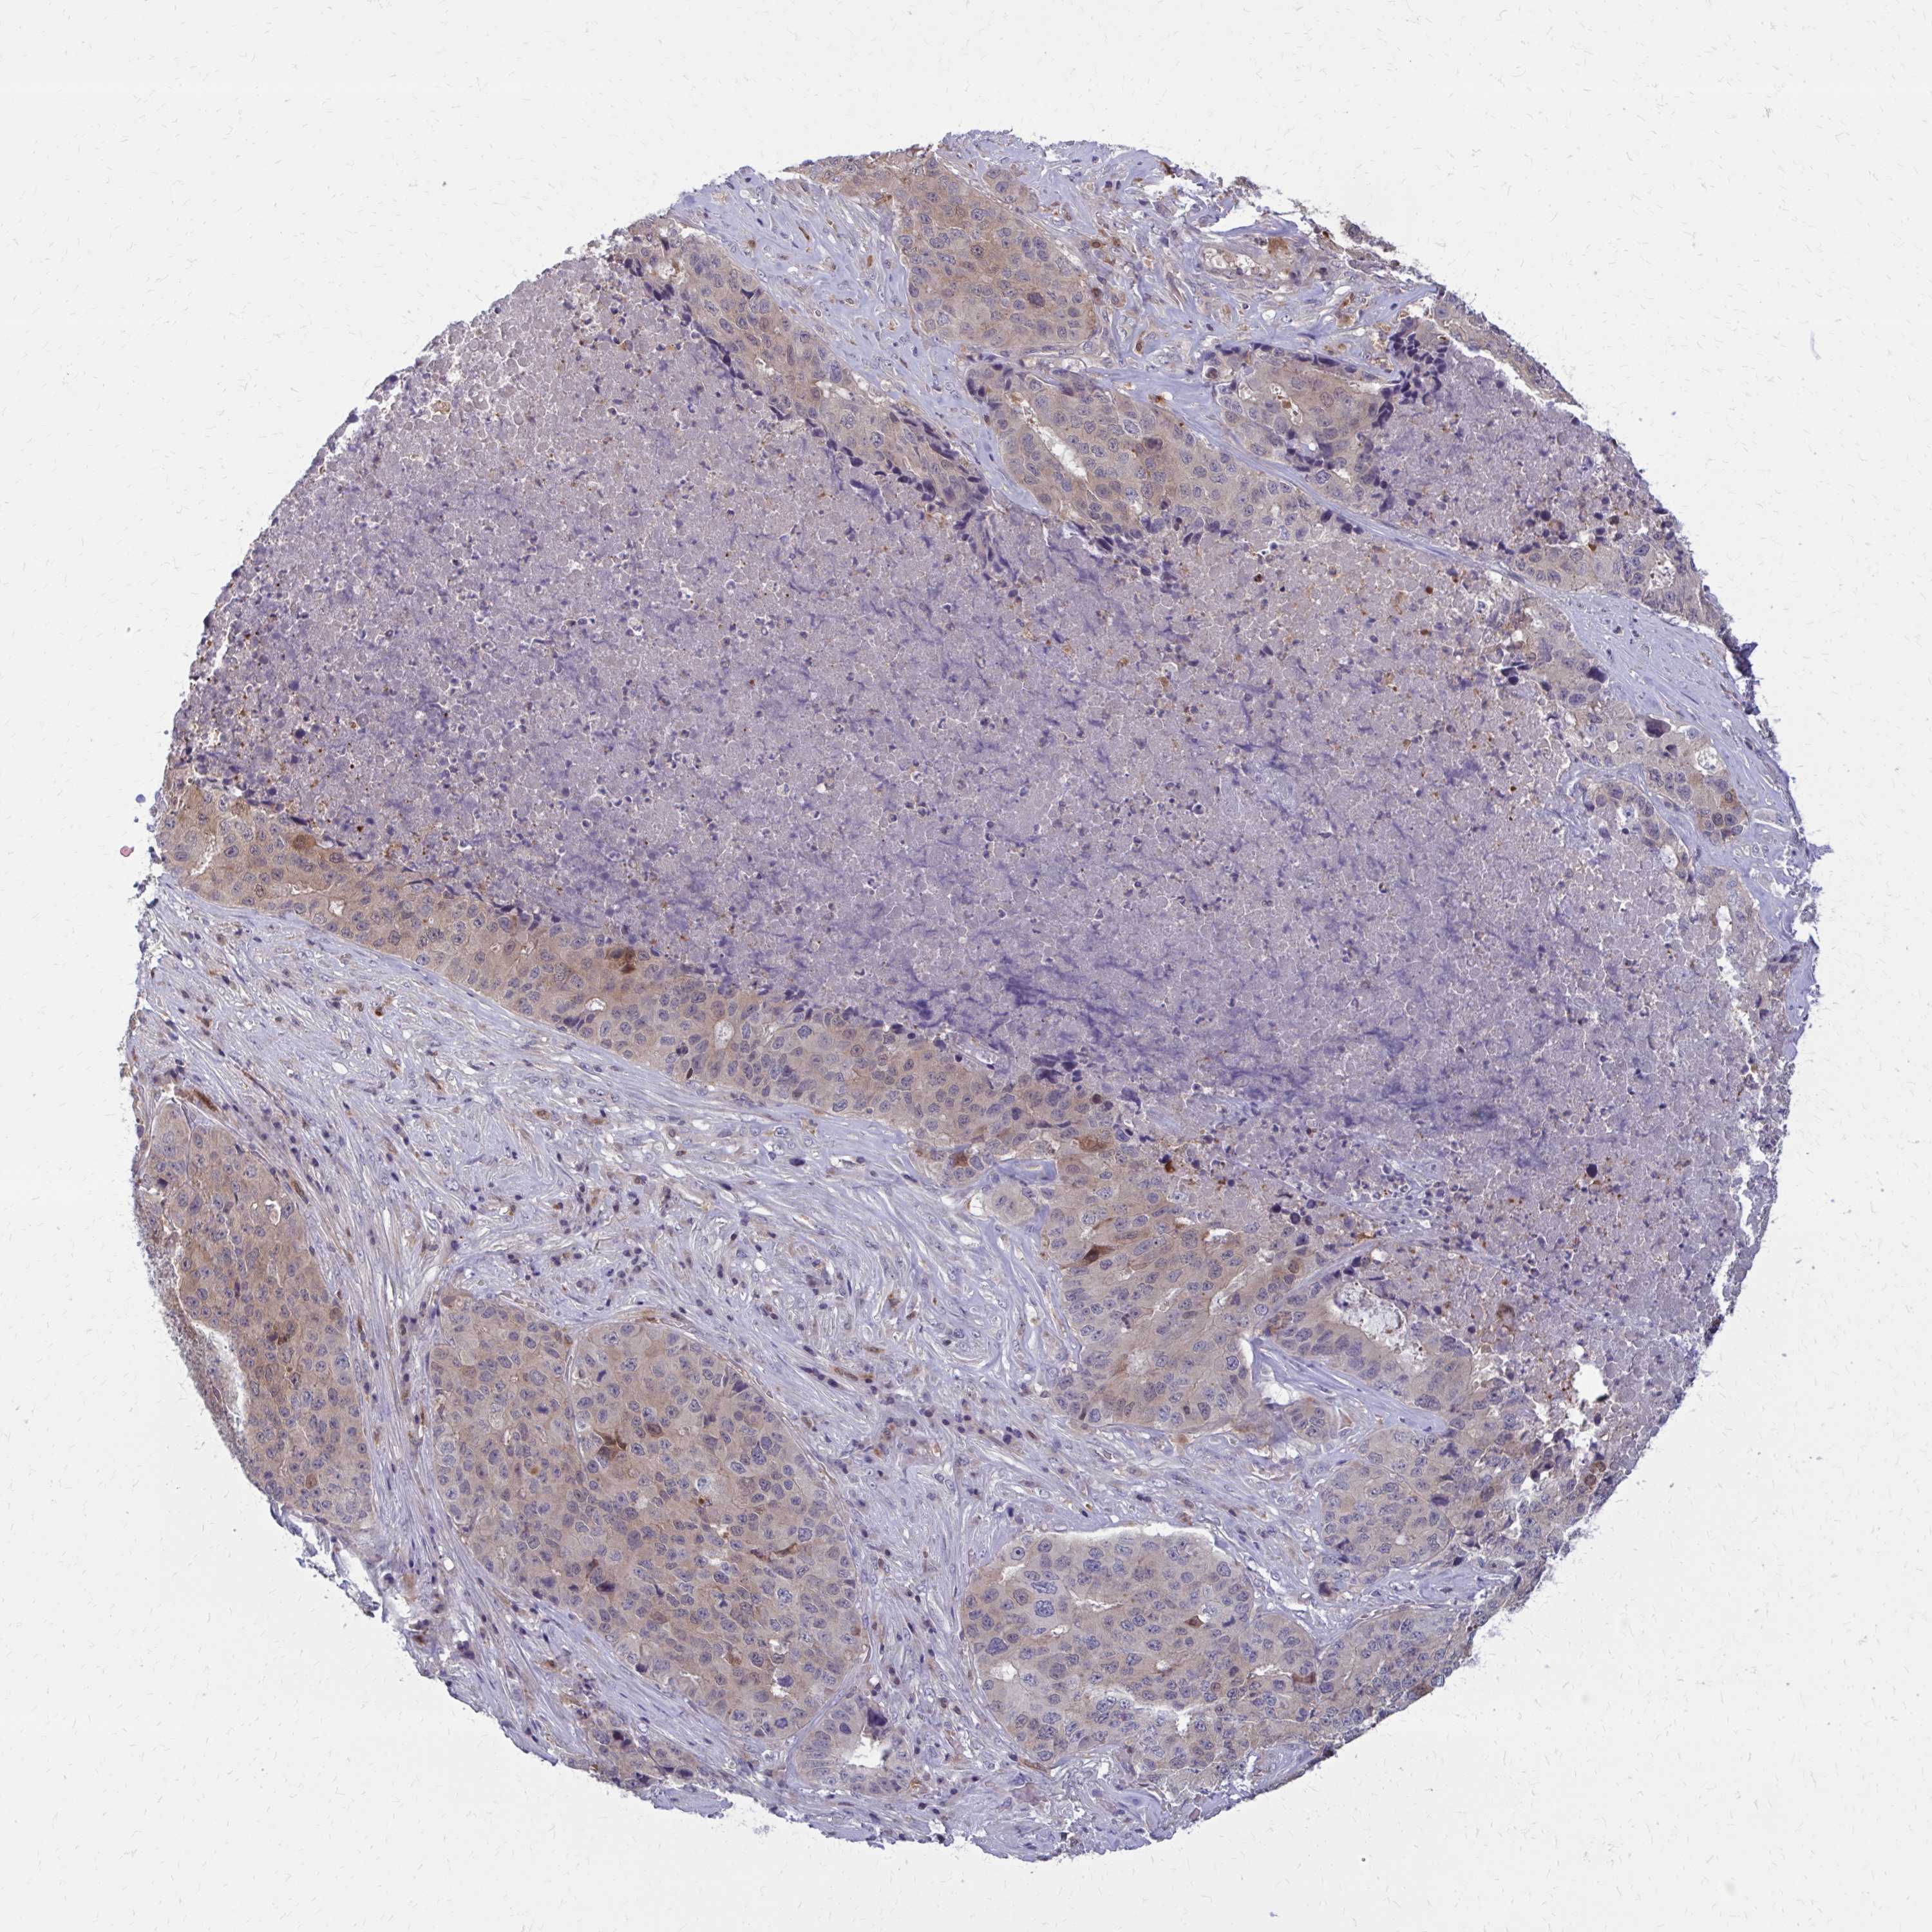

STOMACH CANCER - Protein expressioni

A mouse-over function shows sample information and annotation data. Click on an image to view it in a full screen mode. Samples can be filtered based on level of antibody staining by selecting one or several of the following categories: high, medium, low and not detected. The assay and annotation is described here.

Note that samples used for immunohistochemistry by the Human Protein Atlas do not correspond to samples in the TCGA dataset.

Antibody stainingi

Antibody staining in the annotated cell types in the current human tissue is reported as not detected, low, medium, or high, based on conventional immunohistochemistry profiling in selected tissues. This score is based on the combination of the staining intensity and fraction of stained cells.

Each image is clickable and will lead to virtual microscopy that enables deeper exploration of all samples and also displays staining intensity scores, fraction scores and subcellular localization as well as patient and tissue information for each sample.

Antibody HPA051428

Staining

High

Medium

Low

Not detected

Intensity

Strong

Moderate

Weak

Negative

Quantity

>75%

75%-25%

<25%

None

Location

Nuclear

Cytoplasmic/membranous

Cytoplasmic/membranous,nuclear

Adenocarcinoma, NOS